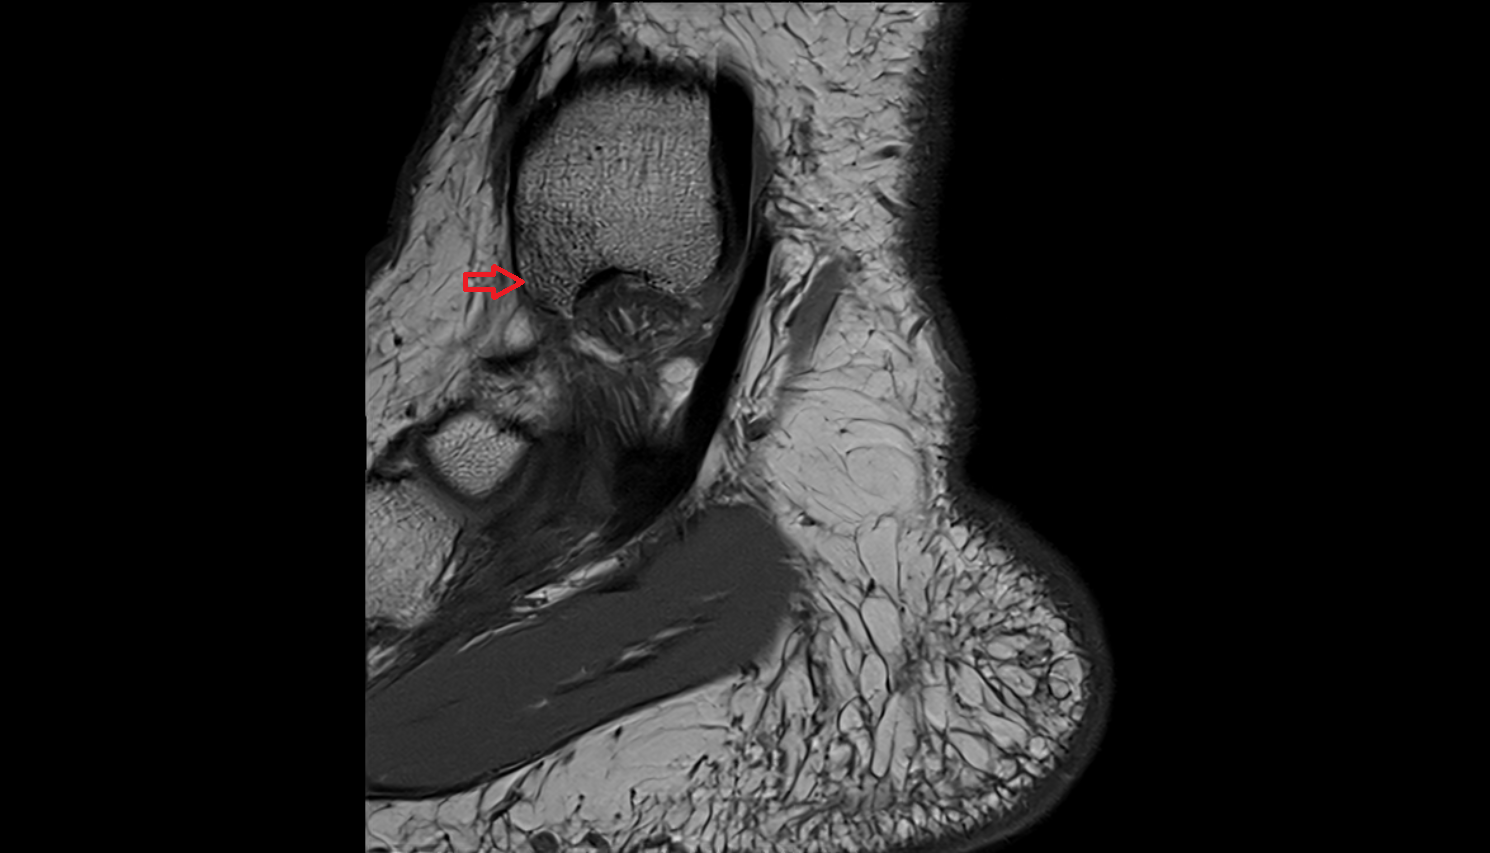

- Ankle joint

- Talus

- Calcaneus

- Anterior talofibular ligament

- Posterior talofibular ligament

- Deltoid ligament complex